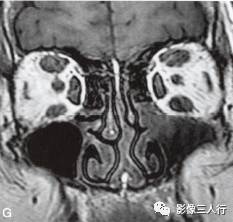

A~C.抑脂T2WI横断面;D~F.T1WI横断面;G~H.T1WI冠状面;I.抑脂T2WI冠状面

横断面显示双侧眼球明显突出,双侧眼球角膜至双侧颧突连线的垂直距离分别为:右侧2.2cm、左侧2.3cm。双侧眼外肌明显增粗,以双侧内、外、上、下直肌明显,短径均可达7mm,且以肌腹增粗明显呈梭形,T1WI等信号(图D~F,图G~H),抑脂T2WI呈明显高信号(图A~C,图I)。双侧眼眶内及球后脂肪增多,双侧眼球内侧至眼眶内侧壁的脂肪厚度增宽。双侧视神经形态及走行正常,双侧眼球晶体、玻璃体形态及信号正常。

影像学检查可帮助该病的诊断与鉴别诊断。CT表现为眼外肌增粗,主要为肌腹增粗,附着于眼球壁上的肌腱不增粗,少数也可同时累及眼外肌肌腹和肌腱。最常累及下直肌,其次为内直肌、上直肌和上提肌,偶尔累及外直肌。MRI表现为受累的眼外肌T1WI低信号,T2WI高信号,压脂T2WI为高信号;晚期眼外肌已纤维化,在T1WI和T2WI均呈低信号。增强扫描急性期时增粗的眼外肌有轻至中度强化,晚期眼外肌纤维化时则无强化。眶内脂肪体积增多表现为球周脂肪尤其是眶前部脂肪的增多。本例影像征象较典型。